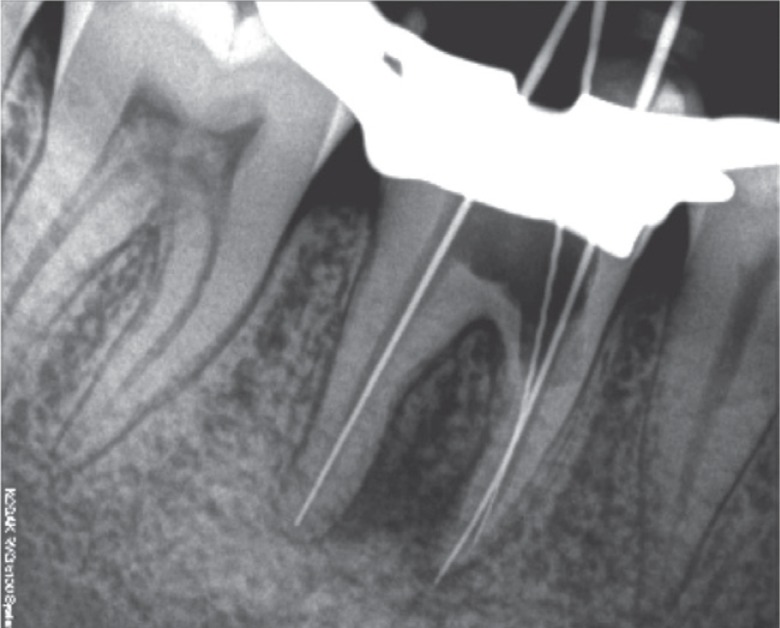

Figure 3Working length determination radiograph.